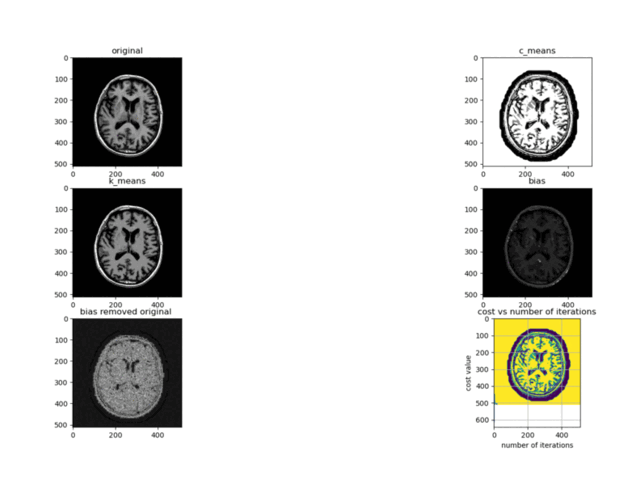

NeuroCluster is an advanced image segmentation toolkit leveraging the Improved Intuitionistic Fuzzy C-Means (IIFCM) algorithm, specifically tailored for magnetic resonance (MR) image analysis. This toolkit enables precise segmentation of MR images into distinct regions, enhancing the ability to identify and analyze various brain structures based on pixel intensity and color values.